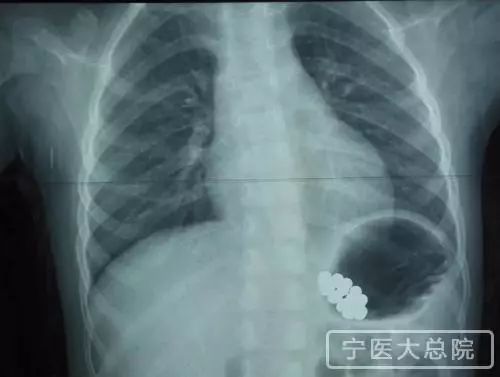

近日,宁夏医科大学总医院收治了一名3岁的小女孩,她将22颗磁力珠吞进了肚子,沉甸甸的坠在胃里,十分危险。

医生为她做了检查,医学影像显示,佳佳胃里的22颗磁力珠磁性非常强,已经相互吸引在了一起,形成一个椭圆形的整体,肯定无法自行排出体外。